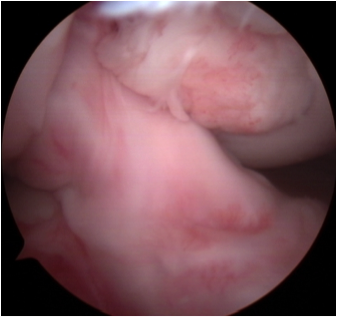

靭帯再建術後